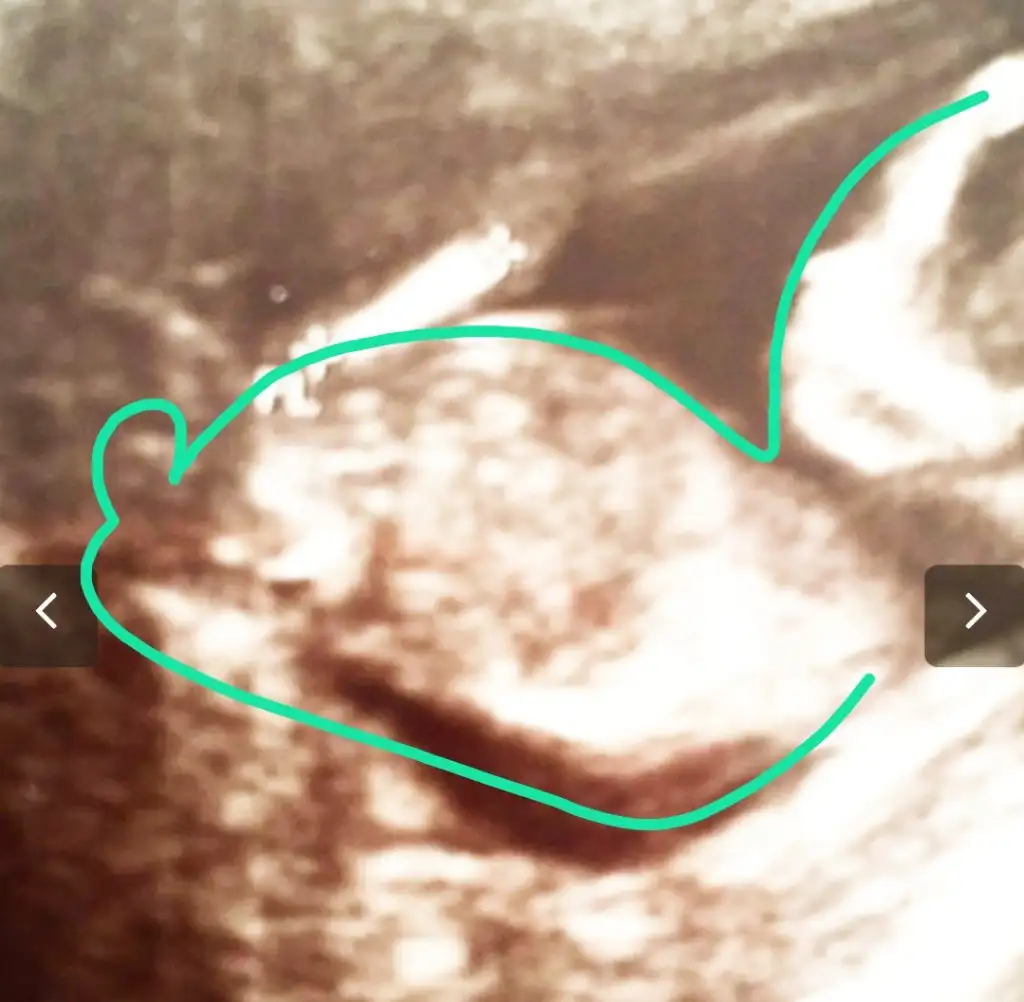

Merhaba daha önce görümcemin bebeginin cinsiyetini bildiniz. Şimdide yiyenin için rica ediyorum bakarmısın lütfen. 12 hafta karından. Ikra meyra Ikra meyra

Belkide kızdır çünkü çıkıntı gördüğüm nub ise erkek sanki dedim başka USG varmi